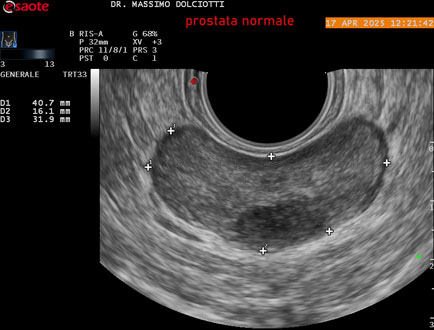

Data inserimento: 01/10/2025

Ecografia del: 17/04/2025

Strumento: Esaote MyLab Eight

Sonda: Convex Multifrequenza 1-8 MHz, Endocavitaria Multifrequenza 3-9 MHz e 3-13 MHz

Età Paziente: M 35 anni

Motivazione dell'esame: disuria.

Commento all'esame: le immagini ed il video documentano la prostata di ecostruttura regolare e morfovolumetria normale con diametro trasversale di 40 mm, diametro anteroposteriore di 21 mm e diametro longitudinale di 43 mm, con volume prostatico calcolato di 18 cc (v.n. < 20 cc), il profilo prostatico è regolare e netto, non si documentano calcificazioni intraghiandolari, la vascolarizzazione della ghiandola è normale. La vescicola seminale destra presenta diametro longitudinale di 44,4 x 7,8 mm, la vescicale seminale sinistra ha diametro longitudinale di 45,3 mm x 7,2 mm.

Conclusioni: prostata normale (normal prostate).